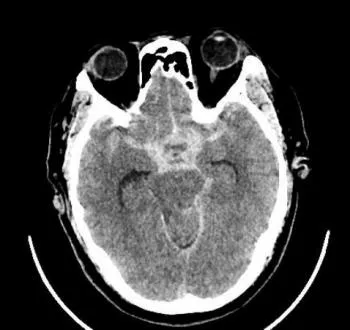

近日凌晨,峨眉山市人民医院急诊科接到内蒙古游客求救电话,55岁的鞠先生来峨眉旅游,突发剧烈头痛、呕吐,救护车随即出发,凌晨2点25分将患者接回医院,急诊头颅CT显示:大量蛛网膜下腔出血。神经外科副主任医师杨志敏立即前往急诊科会诊,根据多年丰富的临床经验,杨志敏医生判断患者为颅内动脉瘤破裂导致的蛛网膜下腔出血,急诊CTA影像结果提示:患者颅内前交通动脉及左侧大脑中动脉分叉处分别有9.5*7.7mm和7.4*5.6mm两个动脉瘤,随时可能再次破裂。